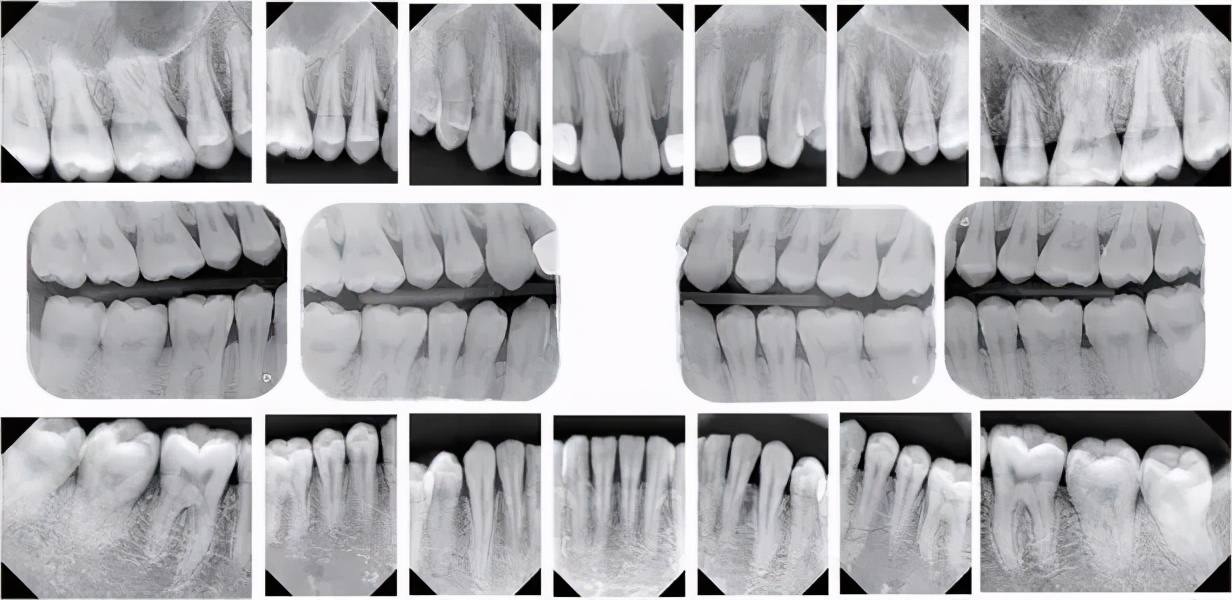

图1

图2

原来自然的很小的拱度(图1)会变得更高更尖。因此阻碍了两鄂必要的伸张,使得后来出的牙齿没有地方,不能正常的生长(图2)。牙齿长得如同屋存形式,全口的牙向前突出呲牙,俗话会意地叫做马齿。因为前面的牙对不起来,妨碍了正常的进食和细嚼,所以发生营养上的障碍。

此外孩子很容易得到颈部和鼻部的病症。因为他不能正确的闭上嘴(图3)。如果孩子因为鼻咽腔息肉被迫不得不用嘴呼吸,也会发生同样的不良现象。此外由不洁的(例如掉下来的)假奶嘴也很有感染疾病的危险。

图3